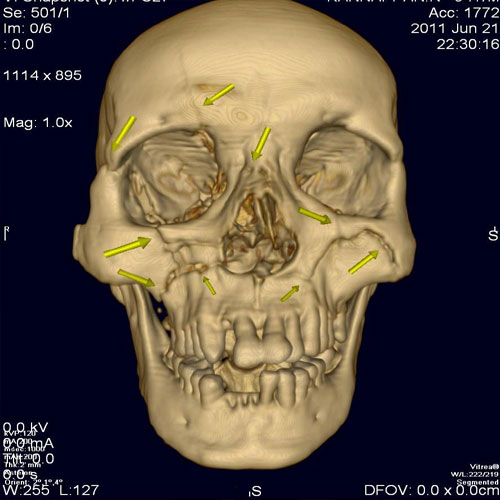

54 year old male with injury to face, CT with 3 D reconstruction shows multiple fractures of facial bones.